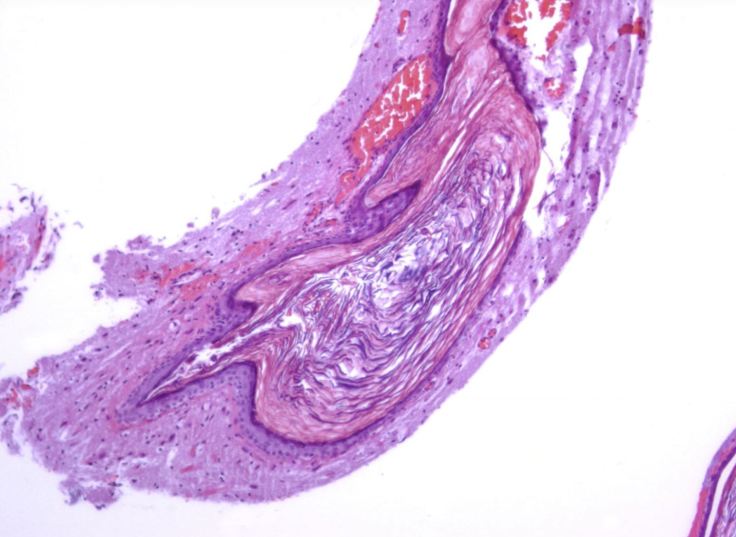

Epidermoid cysts (pictured here with surrounding brain tissue) are histologically characterized by a thin layer of squamous epithelium similar to the epidermal lining the skin. However, unlike skin (which sheds its outer layer of dead cells into the environment), the keratin debris of the sloughed-off upper layer of the epidermoid cyst build up within the cyst center resulting in progressive growth in overall size. If the cyst ruptures it may spill the dead keratinous debris causing a potentially life-threatening chemical meningitis and/or meningoencephalitis.